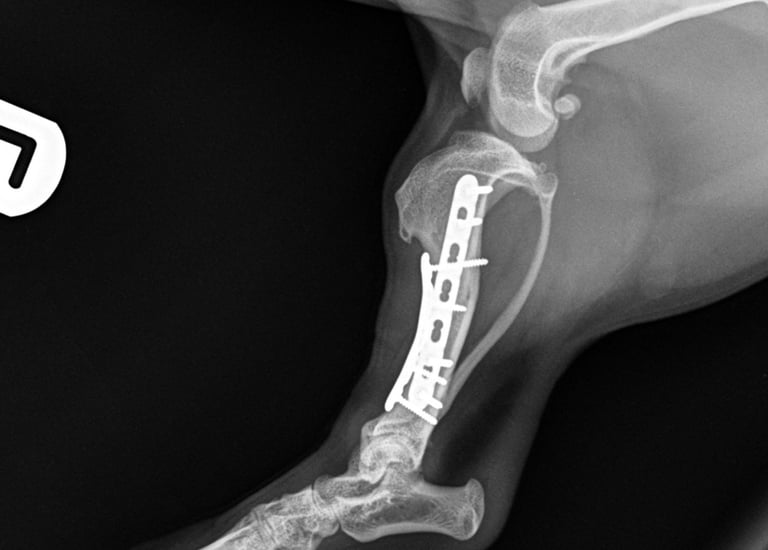

The fracture site was identified and anatomically reduced using bone-holding forceps. Internal fixation was achieved using dual plating in an orthogonal configuration, providing optimal mechanical stability.

Medial plate: A 1.5 mm 7-hole locking compression plate (LCP) was applied in bridging fashion, secured with two bicortical locking screws in both the proximal and distal fracture fragments.

Cranial plate: A 1.5 mm 5-hole LCP was also applied in bridging mode, with two locking screws in the proximal fragment (the most proximal bicortical and the distal monocortical due to proximity to the fracture line), and two bicortical locking screws in the distal fragment.

Postoperative radiographs confirmed excellent implant positioning, appropriate fracture alignment, and good apposition of fracture ends (Fig. 3 and 4).

Fig. 3